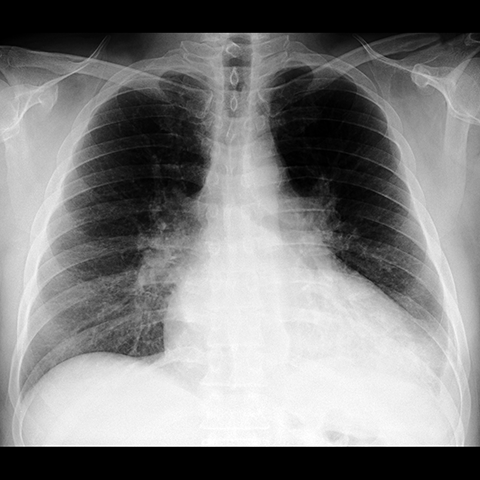

Pleural Effusion, Small to Moderate [1 of 5]